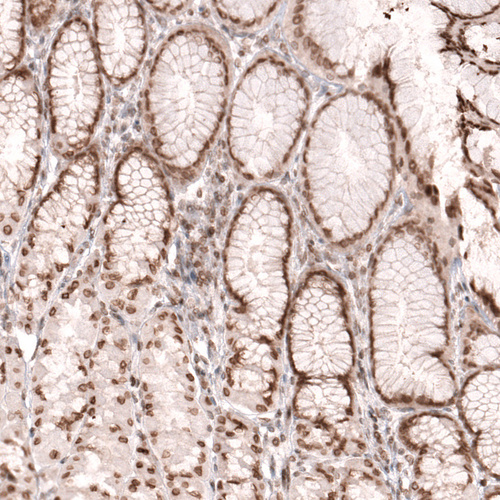

Immunohistochemical staining of human placenta shows moderate to strong nuclear membrane positivity in trophoblastic cells.